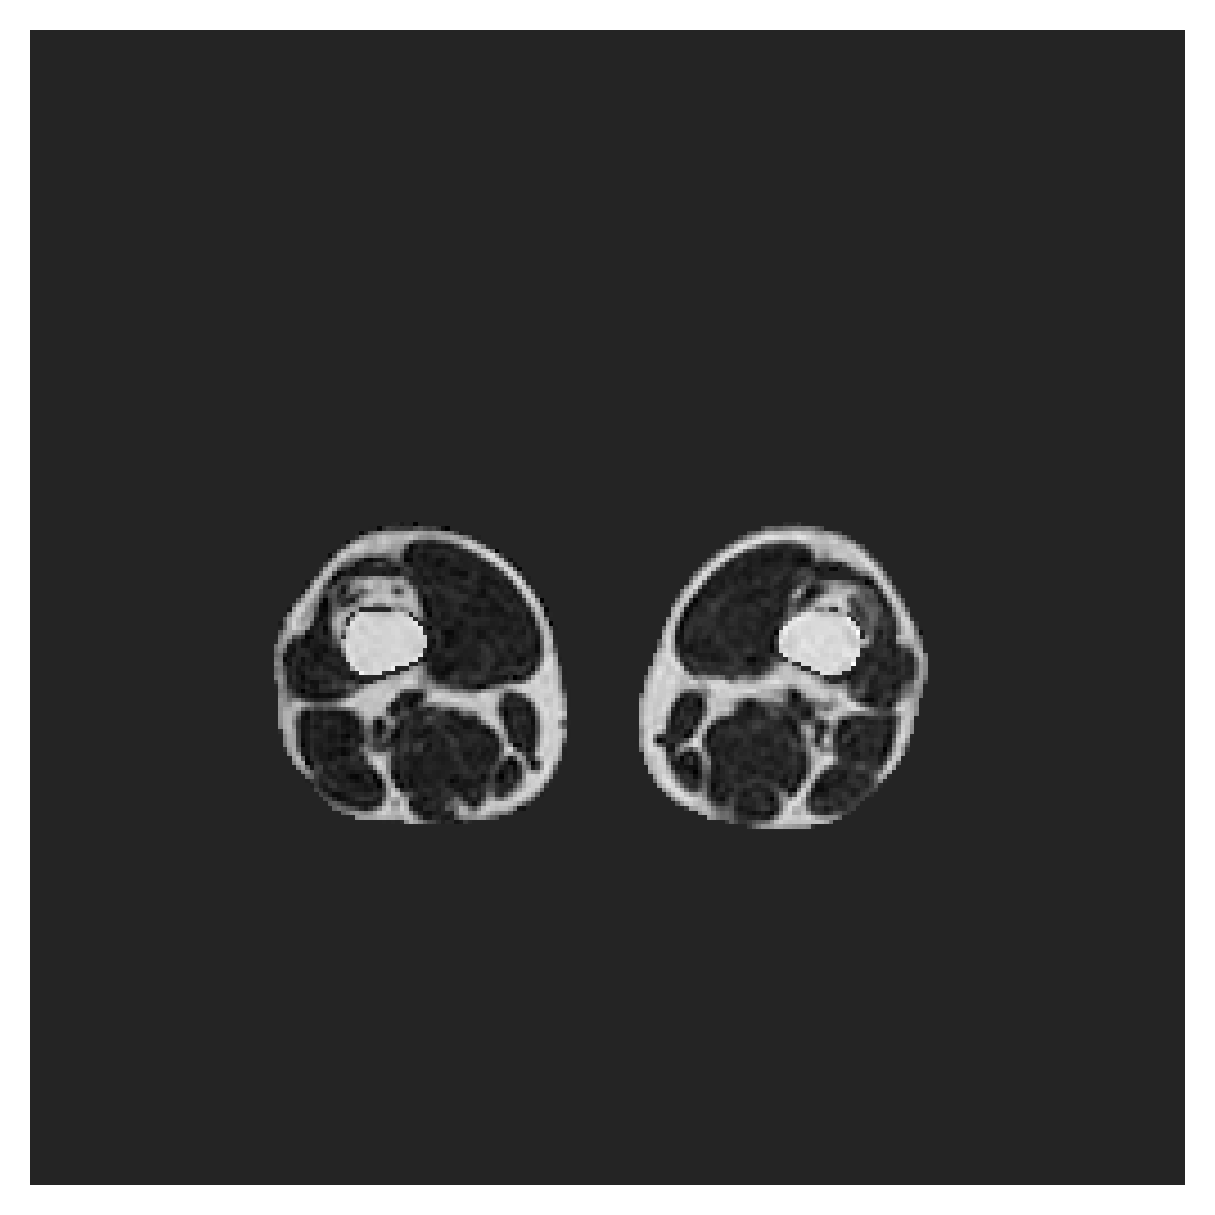

We normalize the volumes and resize the slices to pixels. As the official dataset comes with full annotations, we create a synthetic point ground truth. This is done by first randomly choosing the centers of the point annotations within the class masks, followed by filling an ellipse with axes lengths of and (in pixels) around each center. The intersections of these elliptic discs with the underlying full annotations are then used as our point ground truth. See Figure 2 for an example of the created weak annotation mask. The point annotations are created for every slice, one for each foreground object present in the slice.